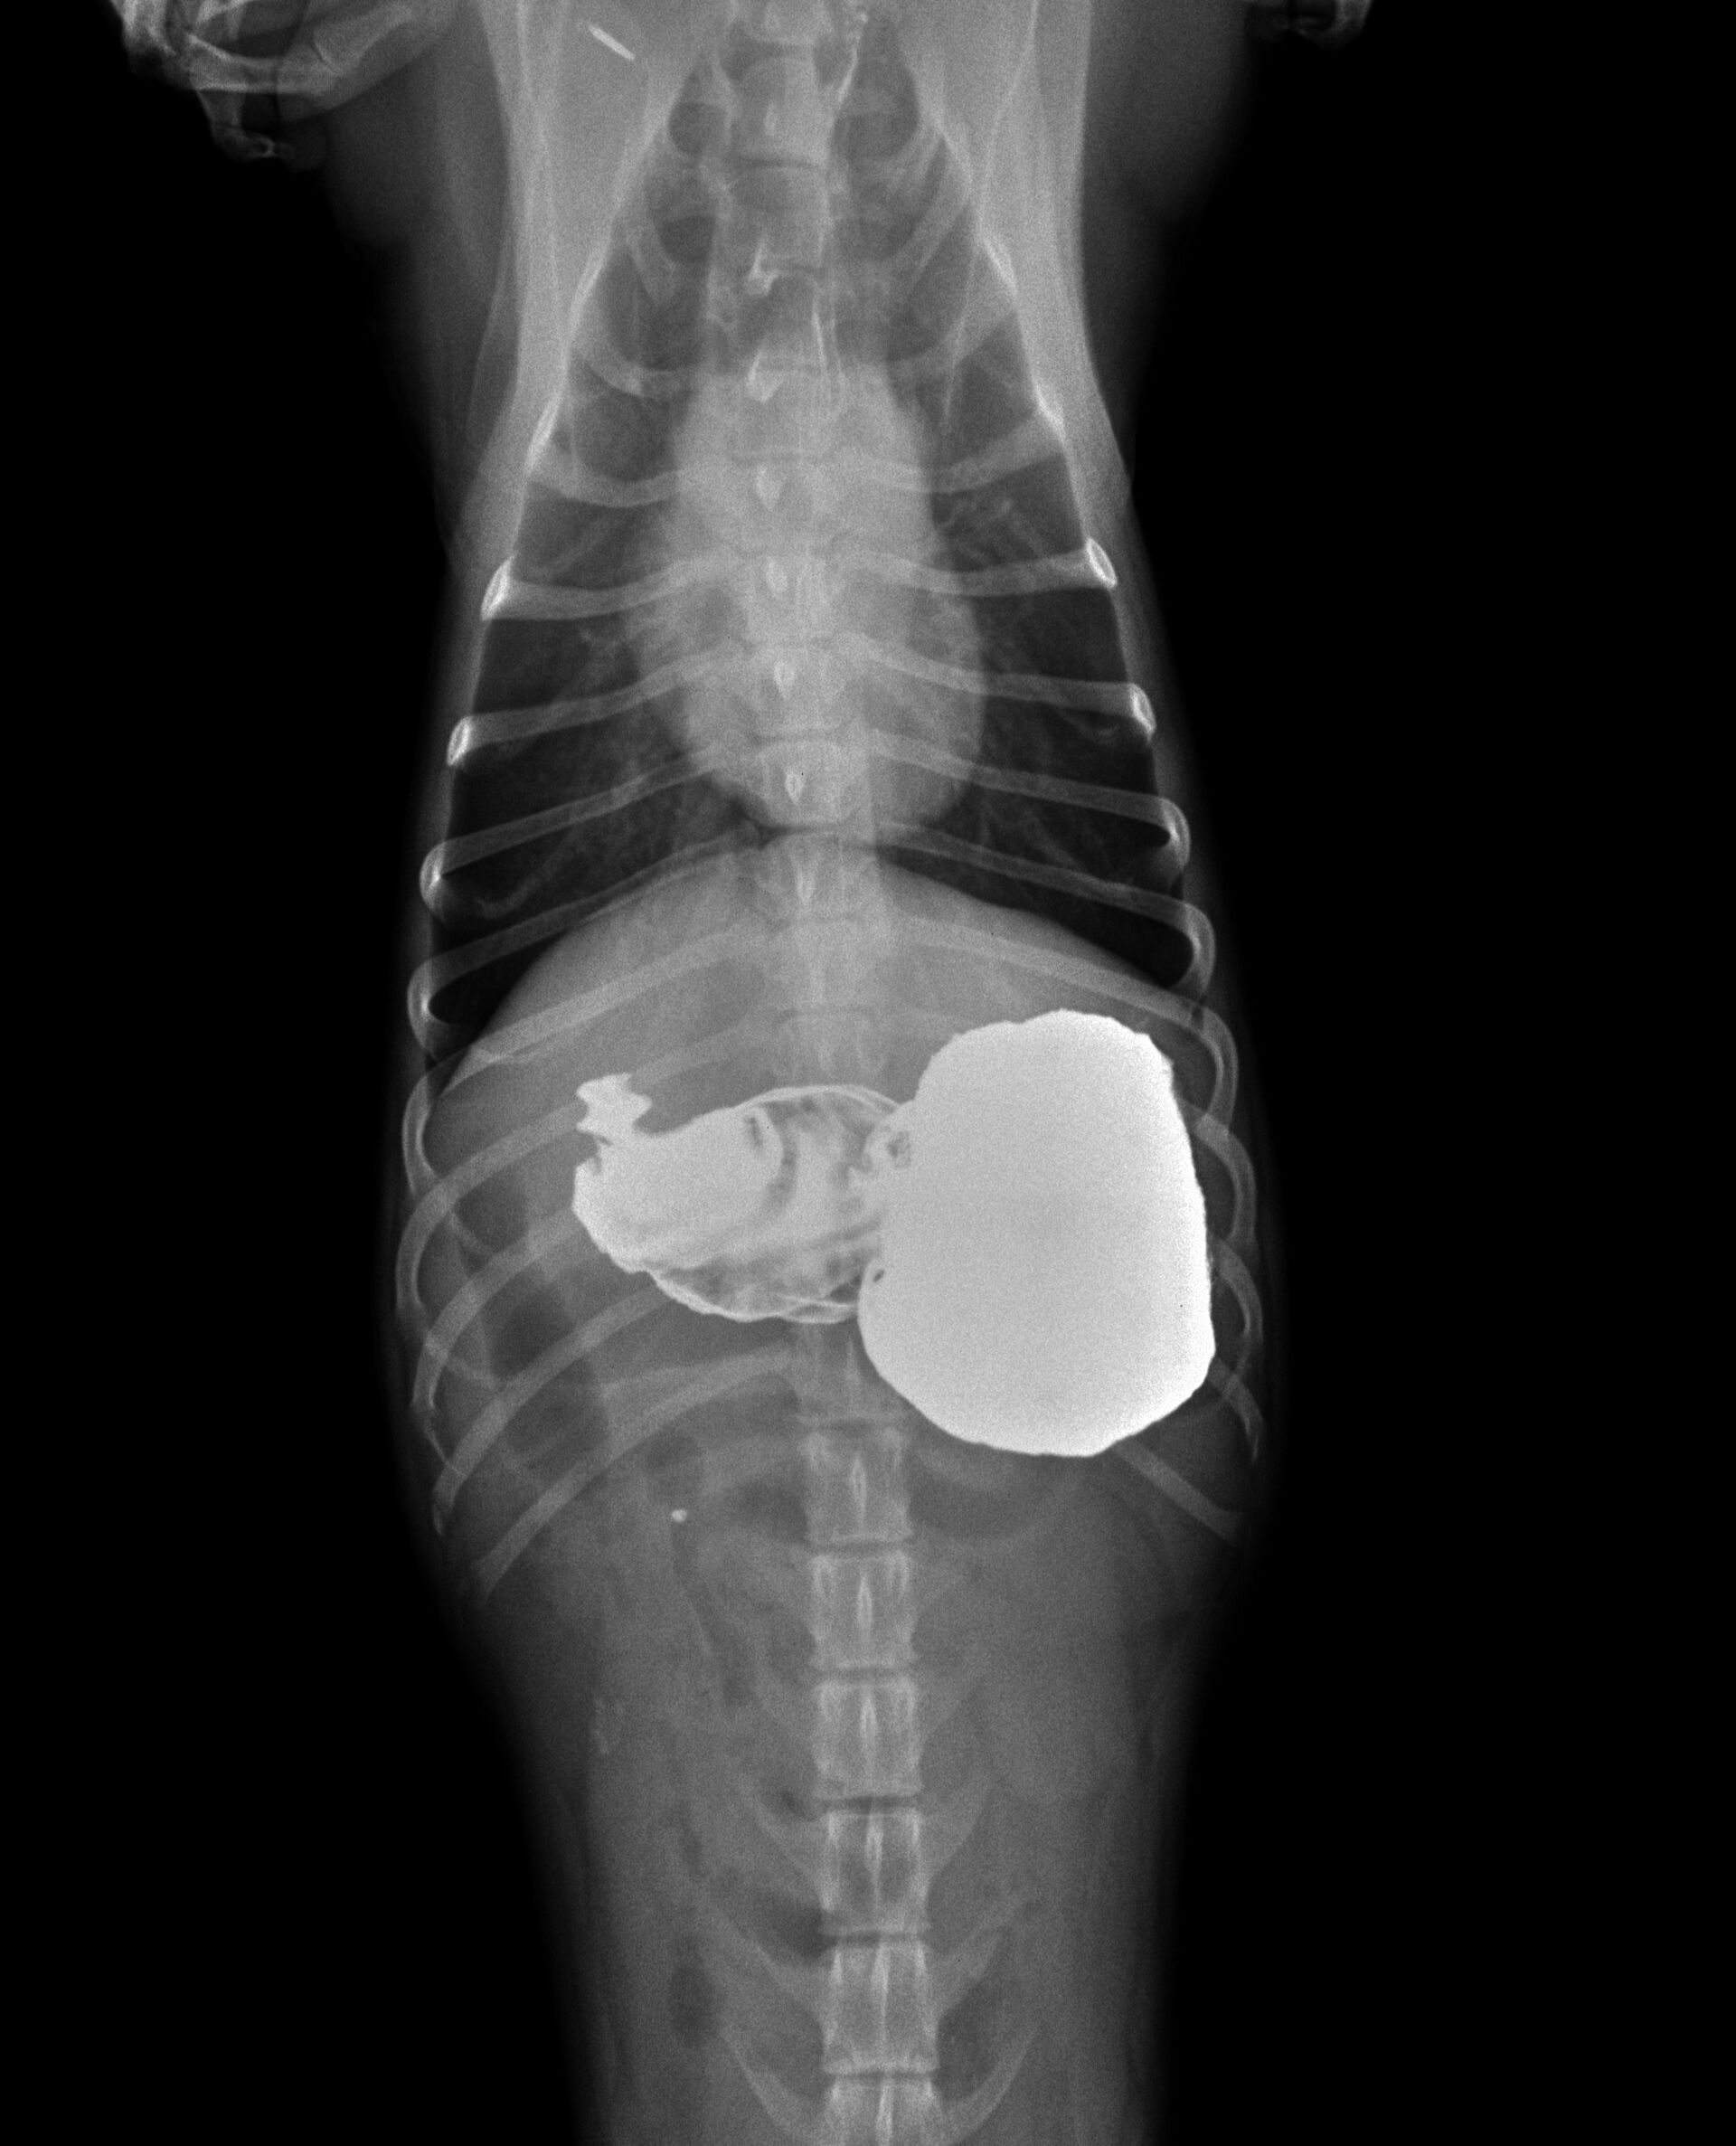

胃から十二指腸にかけて普通より少しガスが多く認められました。益々異物による腸閉塞が疑われたので、バリウム検査を行うことにしました。その結果が以下です。

黄色矢印のところでバリウムが止まって円形の異物のようなものが認められました。その後もバリウム投与後2時間までレントゲンを撮影しましたが、矢印のところからは全く進みませんでした。異物によって腸閉塞していることは疑いがありませんでしたので、手術を行いました。下の写真のように小腸内に異物が認められ、腸を切開し、異物を取り除きました。飼い主さんにお見せしたところ、いつも遊んでいるおもちゃの突起物であることがわかりました。